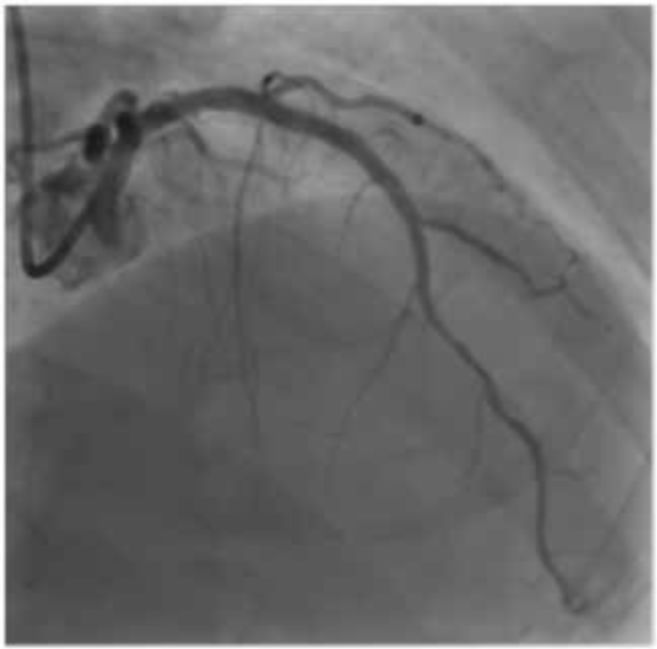

本次主诉:静息胸痛,经本院检查疑为不稳定性心绞痛并进行CAG,确认#1 90%,#6 75%,#7 90%。

#6~7支架内50%弥漫性狭窄,#11 75%,三枝病变,同日RCA PCI,#1内放入Xience Xpedition 3.5 mm×23 mm,4日后LAD PCI。(图1)